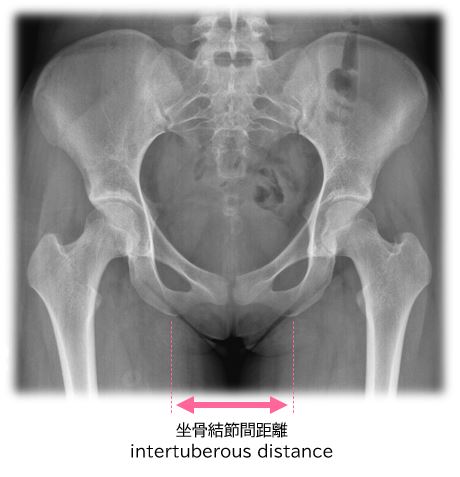

日本人女性の坐骨結節間距離の平均は約11cmですが個人差があります。自転車のサドルは坐骨結節間の距離を計測して選ぶべきです(Figure 19)。

いっぱんに、女性は男性より坐骨結節間の距離が広く、サドルはそれに合わせて幅広のサドルを選ぶと女性器の痛みが少なくなります。幅の広いサドルは「女性用サドル」として販売されている場合があります。

しかし、これは一般論であって、全ての女性に当てはまるわけではありません。男性よりも骨盤の大きい女性がいたり、女性よりも尻の大きい男性がいたりするように、坐骨結節間の距離は男女間の差よりも、性別無関係の個人差が大きいことが知られています(Figure 20)。

そのため、女性だから「女性用」と言うことではなく、性別に関係なく自分の坐骨結節間距離を計測して、適切なサイズのサドルを選ぶのが良いです。